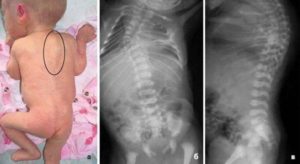

Дисплазия тазобедренных суставов

Достаточно подробно эта тема рассмотрена в одноимённом выпуске передачи «Школа доктора Комаровского». В основе болезни лежит нарушение нормального взаимодействия между головкой бедра и суставной впадиной. Последняя изначально слабо развита и не может нормально выполнять функцию опоры.

Врожденные поражения бедра являются самыми частыми в этой группе заболеваний (до 80%). Этой болезни в основном подвержены девочки – у них она встречается в пять раз чаще. Для заболевания характерно одностороннее поражение (обычно левого сочленения).

При воздействии любого из перечисленных факторов нормальное развитие скелета замедляется. Это приводит к тому, что к моменту появления движений в тазобедренном суставе его составные части остаются незрелыми. Чаще всего процесс располагается в вертлужной впадине – углублении в костях таза. В норме она круглая и глубокая, имеет плотный хрящевой край и служит местом прикрепления связок.

Дисплазия делает все эти образования не подходящими по форме головке бедренной кости. Впадина становится плоской и неровной, что приводит к «выпадению» из неё головки бедренной кости. В результате повторяющихся смещений нарушается кровообращение. Недостаток питательных веществ делает развитие сустава замедленным.

Признаки

Существует специальный симптом «щелчка» — при дисплазии он связан с выскальзыванием головки бедра из неразвитой впадины. Малыша кладут на спину и сгибают ножки, приводя их к животу. Затем они разводятся в стороны и снова соединяются вместе.

При этой болезни в момент разведения и сведения возникают характерные «щелчки». Если этот симптом выявляется до месяца жизни – то, возможно, это вариант нормы, связанный со слабостью мышц бедра.

Существует ряд «малых» признаков:

- При пеленании можно заметить, что складки на бедре и под ягодицами находятся не на одном уровне.

- Согнутые ножки плохо разводятся в стороны.

- Больная конечность немного короче здоровой, а также повёрнута кнаружи.

Невозможность нормального разведения ножек говорит о дисплазии

А вот когда у ребенка щелкают тазобедренные суставы, положение скорее всего серьезное. Щелканье при разведении ног младенца в стороны, когда он лежит на спине, возможно при дисплазии тазобедренного сочленения.

Дисплазия диагностируется при врожденном нарушении сустава (либо он недоразвит, либо у него патологическая подвижность). Это приводит к вывиху или подвывиху головки бедра.

Щелканье (синдром щелчка) происходит, когда вывихнутая головка бедренной кости становится в нормальное положение.

Еще одним симптомом дисплазии является плохое разведение ножек ребенка. У здорового малыша в семь-восемь месяцев они разводятся до 60-70 градусов, при дисплазии – на 40-50 градусов.